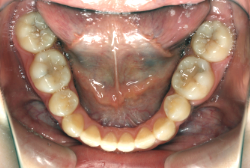

叢生(そうせい)

凸凹な歯並びのことを叢生といいます。矯正歯科に来院する患者様の主訴の中で、最も多いのが「配列の凸凹を真っ直ぐにしたい」というものです。歯の大きさと顎の大きさの調和がとれていないことが原因です。

凸凹を主体としたケースの場合、当院の平均治療期間は18ヶ月ですので、このケースは少し長めに経過しました。理由の一つは凸凹の程度がかなり重症だったと言うことですが、もう一つは、右下第2大臼歯が45度くらい前傾していたため、それを整直化させるために時間を要したと考えています。いずれにしても最終結果は大変よい状態と思います。

治療前は並びが乱れて見た目が悪いというのはもちろん問題ですが、歯科医学的に一番困るのは噛み合わせが悪いという点です。上下の犬歯(3番目の歯)は、上下的に離れた位置にあるため接触することができません。つまり歯としては存在していても、歯としては機能していないということです。